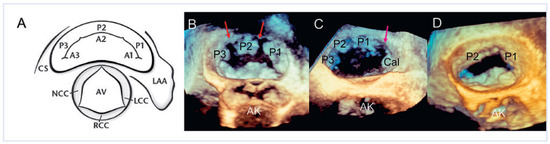

Dreidimensionale Echokardiographie zur Beurteilung der Mitralklappe

Using two-dimensional echocardiography, the complex anatomy of the mitral valve needs mental reconstruction into its three-dimensional shape. The power of both transthoracic and transesophageal three-dimensional echocardiography (3DE) lies in its possibility of showing the complex mitral valve anatomy in one single image, as [...] Read more.

Using two-dimensional echocardiography, the complex anatomy of the mitral valve needs mental reconstruction into its three-dimensional shape. The power of both transthoracic and transesophageal three-dimensional echocardiography (3DE) lies in its possibility of showing the complex mitral valve anatomy in one single image, as opposed to the mental reconstruction based on multiple two-dimensional images and schematic assumptions. Several 3DE modalities are used in daily life, including real time (“live”) modes as wells as postprocessed images. 3DE is of special interest in the evaluation of mitral stenosis, complex mitral valve prolapse and mitral valve prostheses. It has an established role in the perioperative mitral valve assessment during mitral valve surgery as well as during percutaneous mitral valve procedures. Limitations of 3DE are relatively low frame rates, an important learning curve as well as timeconsuming processing. Full article

Show Figures

Figure 1